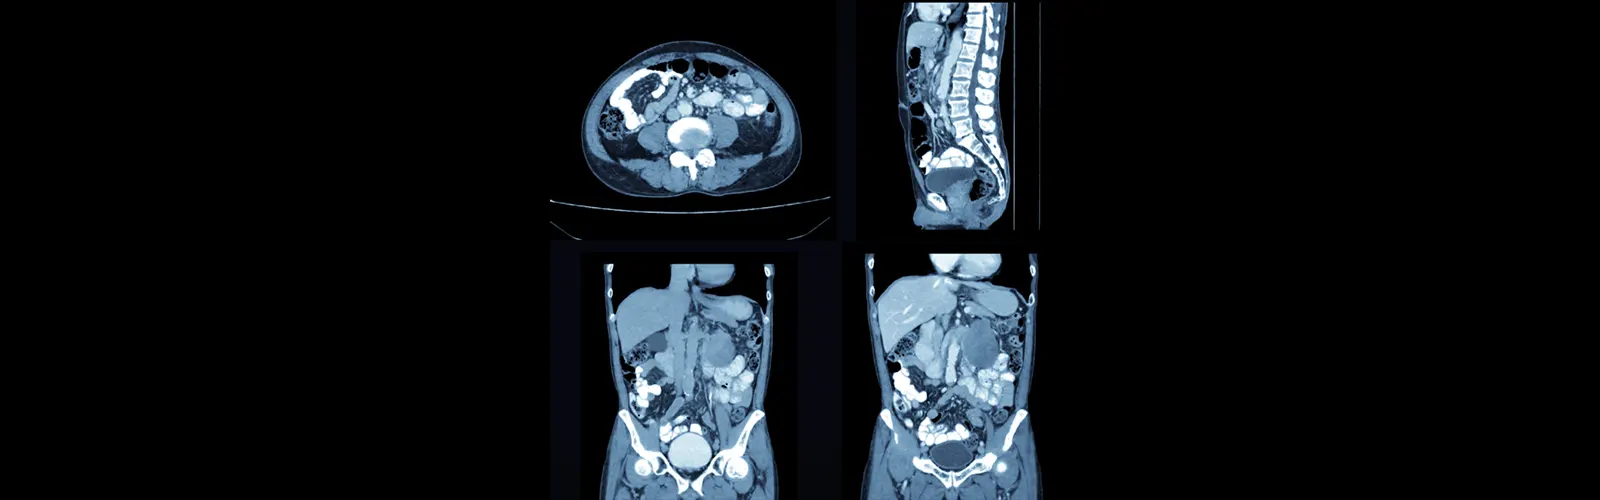

CECT Abdomen stands for Contrast-Enhanced Computed Tomography of the Abdomen. It is a clinical imaging process that makes use of X-rays and a distinction dye to reap distinctive pictures of the belly region.

During a CECT Abdomen, a distinction agent or dye is injected into a vein, which helps to spotlight and decorate the visibility of blood vessels, organs, and different constructions in the abdomen.

The scanner takes more than one X-ray pix from distinctive angles, which are then processed with the aid of a laptop to create cross-sectional snapshots of the abdomen.

These snapshots can grant treasured data about the liver, kidneys, spleen, pancreas, intestines, blood vessels, and different buildings inside the stomach cavity.

CECT Abdomen is often used to diagnose and consider stipulations such as tumours, infections, inflammation, trauma, kidney stones, stomach pain, and abnormalities in the stomach organs.